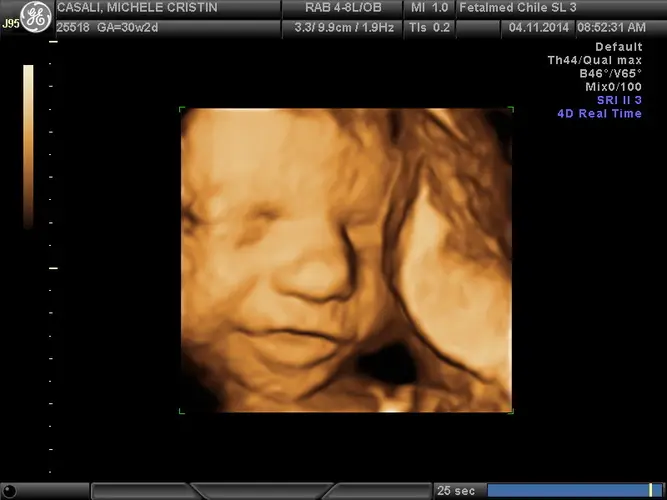

Um dos marcos mais emocionantes desta semana é que os olhinhos do seu pequeno estão começando a se abrir. As pálpebras ficaram fechadas durante os últimos meses para permitir o desenvolvimento completo da retina, que é responsável por focar as imagens. Embora a íris ainda não tenha muita pigmentação – sendo ainda cedo para determinar a cor definitiva dos olhos – seu bebê já consegue enxergar, o que representa um avanço imenso no seu desenvolvimento sensorial.

O cérebro também passa por desenvolvimentos importantes. As ondas cerebrais estão se aperfeiçoando, especialmente nos sistemas visual e auditivo. A audição do bebê está completamente desenvolvida, e ele já responde a estímulos sonoros – você pode notar que os batimentos cardíacos dele aceleram temporariamente quando há ruídos externos. Ele pode até mesmo reagir à sua voz ou à música que você escuta!

Se você ainda não fez o ultrassom morfológico de segundo trimestre, esta pode ser uma das últimas oportunidades para realizá-lo dentro do período ideal. Este exame é fundamental para avaliar a anatomia fetal detalhadamente e verificar se tudo está se desenvolvendo adequadamente.